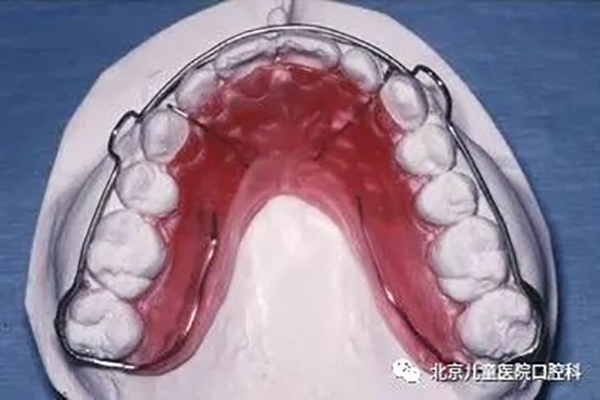

1、Hawley保持器:矫治结束后有利于深咬合的控制,并允许后牙少量调整达到更紧密的咬合关系。

2、环绕式保持器:此类保持器主要用于防止间隙复发。